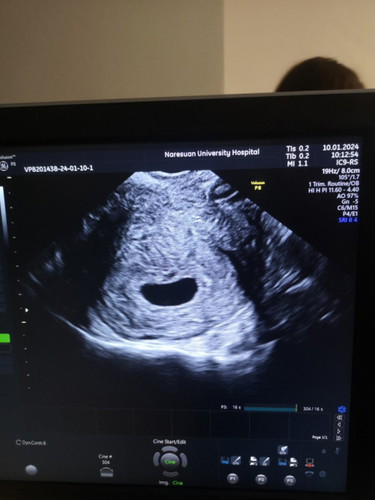

เรา6วีค6วัน ไปอัลตร้าซาวด์ผ่านทางช่องคลอด เจอแต่ถุงตั้งครรภ์ ไม่เจอตัวอ่อน แล้วมีเลือดชมพูๆ น้ำตาลออกด้วย 1 วัน คุณหมอเลยเกริ่นว่า อาจท้องลม ติดตามอีก1วีค ใจแป้ว กังวลมากค่ะ คุณแม่ๆอัลตร้าซาวด์เจอน้องช้าสุดกี่สัปดาห์บ้างคะ#ขอบคุณล่วงหน้านะคะ #ท้องแรกคะ #ขอบคุณสำหรับคำตอบค่ะ